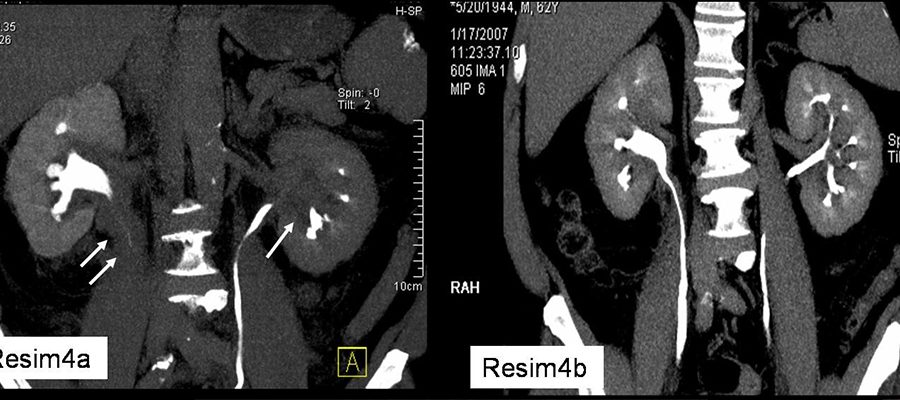

Üriner Sistem Tomografi

Bu tetkikte böbrek, üreter , mesane gibi üriner sistem yapılarında taş, tümör v.b patolojileri aramak için yapılır.Taş oglularında kontrast madde kullanımına gerek olmamaktadır.Ancak özellikle üst ve alt üreter taşlarının üriner sistemde ne derece tıkanıklık yapıp yapmadığını görmek amacıyla kontrast madde kullanılabilir.Yine böbrek ,mesane, üreter tümörlü vakalarda kontrast ajan kullanılabilmektedir.

Renal kolik yani böbrek taşı olan hastalarda düşük doz  BT taraması ile böbrek, mesane ,üreter taşları rahatlıkla görüntülenebilmektedir.